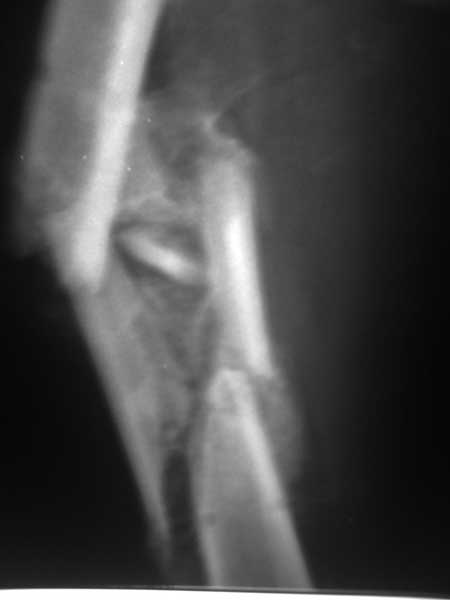

Пациент 39 лет. Травма в ДТП 2.5 месяца назад. Тяжелая сочетанная травма. ЗЧМТ. Тупая травма живота. Разрыв селезенки. Надрывы печени. Перелом бедра. При поступлении лапаротомия. Спленэктомия. Фиксация перелома бедра стержневым аппаратом. в последующем инфаркт мозга на фоне жировой эмболии. длительное нахождение на ИВЛ. Обширный пролежень в области крестца. и т.д.в настоящее время состояние больного стабилизировалось. активизирован на ходунках.имеется деформация бедра, укорочение 10 см. гранулирующий пролежень в области крестца. патологической подвижности в зоне перелома не отмечается.Оптимальные сроки проведения реконструктивной операции на бедре? Сейчас? Или после окончательного сращения?

А откуда такое укорочение взялось, 10см? По представленному фрагменту рентгенограммы понять трудно. В любом случае, если состояние пациента позволяет оперировать сейчас, зачем откладывать операцию до формирования монолитного сращения?

Конечно, снимки для планирования надо нормальные, не такой огрызок.

Можно закрыто мобилизовать отломки, наложить дистракционный аппарат, восстановить ось и длину, да и заштифтовать, на всякий случай с антибиотиковым цементным покрытием.

Спасибо за снимки. Предложения по тактике прежние.

Попробовать-то можно. И просто руками "об колено", а то и наложить аппарат, приложить флексионные и ротационые усилия прямо за разъединенные секции.

Если уж никак, то сделать чрескожную остеотомию.

Но если картинки недавние, IMHO должно получиться закрыто разобщить.